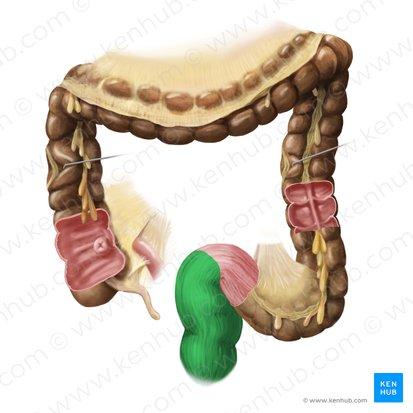

Appendix

a small, finger-like pouch attached to the large intestine.

Spleen

An organ located in the upper left abdomen that is part of the lymphatic system, filtering blood and storing white blood cells

Ileocecal Valve

A sphincter muscle situated at the junction of the ileum and the cecum, which controls the flow of chyme from the small intestine into the large intestine and prevents backflow.

Cecum

A pouch-like structure connected to the junction of the small and large intestines.

Appendix

A small, finger-like pouch attached to the cecum.